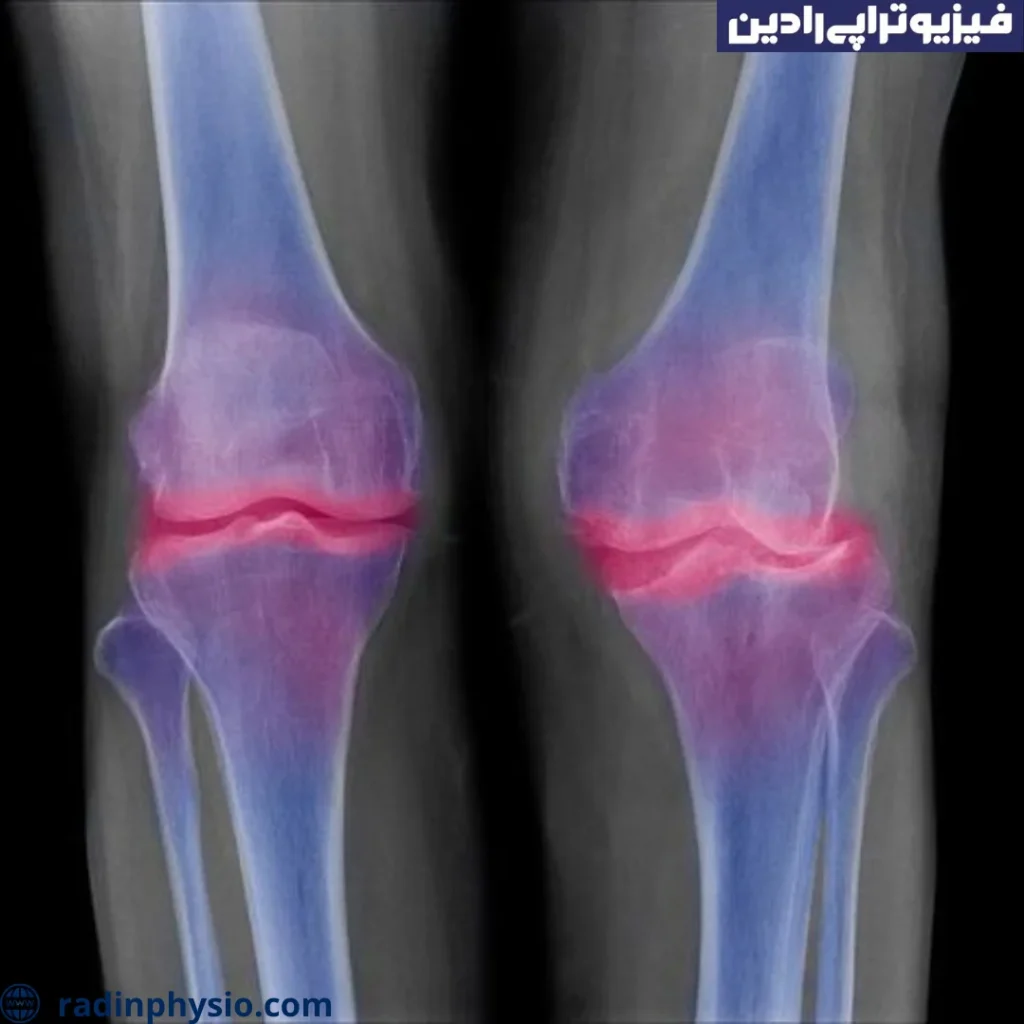

خارهای استخوانی زانو (Osteophyte of the Knee)

خارهای استخوانی در ناحیه زانو، به خصوص در موارد آرتروز زانو (آسیب مفصل زانو)، رایج است. این خارها ممکن است باعث درد، تورم و محدودیت حرکت در زانو شوند.